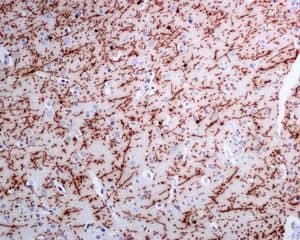

Rabbit Recombinant Monoclonal Myelin Basic Protein antibody. Suitable for IHC-P, WB and reacts with Human, Recombinant full length protein samples. Cited in 5 publications.

Applications IHC-P, IP, WB

Species Reactivity Human